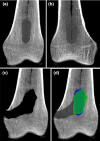

Methods: The expert performed curettage on 20 cadaveric bones prepared with a paraffin wax mixture tumor, 10 freehand and 10 navigated. We re-used 12 bones for the novice experiments, 6 freehand and 6 navigated. Tumor and curettage cavity volumes were segmented on pre- and post-cone-beam CT scans. Accuracy was quantified using the Dice Similarity Coefficient (DSC), and with remaining tumor volume, bone curettage volume, maximal remaining width and procedure times compared between navigation and freehand groups for both users.

Results: There were little differences in curettage accuracy between a navigated (DSC 0.59[0.17]) and freehand (DSC 0.64[0.10]) approach for an expert user, but there were for a novice user with DSC 0.67(0.14) and 0.83(0.06), respectively. All navigated and freehand procedures had some amount of remaining tumor, generally located in a few isolated spots with means of 2.2(2.6) cm3 (mean 20% of the tumor volume) and 1.5(1.4) cm3 (18%), respectively, for the expert and more diffusely spaced with means of 5.1(2.8) cm3 (33%) and 3.0(2.2) cm3 (17%), respectively, for the novice.